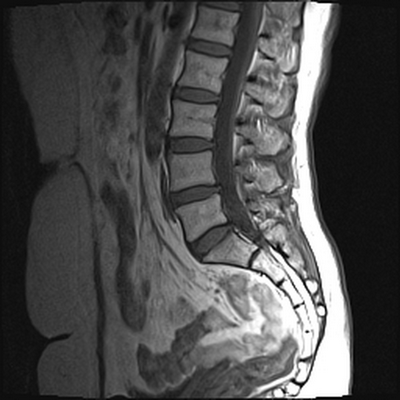

МРТ позвоночника. Т2-взвешенная МРТ, срез через межпозвоночное отверстие. Красные стрелки - корешки. Межпозвоночное отверстие обведено малиновым. P- ножка дуги. VB - тело позвонка.

МРТ позвоночника. Аксиальная Т2-взвешенная МРТ. Нормальный срез через дугоотростчатые суставы.

После того, как появилась ясность в способе получения МРТ изображений позвоночника, надо понять какие анатомические структуры видны. Счет позвонков ведется разными способами - сверху от зубовидного отростка С2 (осевой позвонок), от бифуркации трахеи Т5 ( пятый грудной, с погрешностью на 1 позвонок) или снизу от L5 (последний поясничный), также не исключена погрешность на 1 позвонок в связи люмбализацией или сакрализацией. Анатомия позвоночника в МРТ изображении представлена в нашей другой статье. На серии сагиттальных Т2-взвешенных МРТ позвоночника видны асе основные структуры, причем удается проследить ход корешков конского хвоста. В поясничном отделе он идет под углом вниз и выходит через межпозвоночное отверстие нижележащего позвонка. Аксиальные (поперечные) МРТ срезы всегда делаются вдоль межпозвоночного диска, то есть с учетом нормальных или патологических изгибов позвоночника. Они наиболее удобны для оценки состояния дугоотростчатых суставов. При МРТ позвоночника в поперечной плоскости МРТ срезы часто делают на разных уровнях для лучшей визуализации состояния корешков по их ходу - в дуральном мешке, затем боковом кармане дурального мешка, далее в межпозвоночном отверстии и, наконец, после выхода из него. Таким образом, в поперечном МРТ срезе позвоночника через межпозвоночное отверстие на поясничном уровне можно видеть отрезки сразу двух корешков - вышележащего на выходе из отверстия, и нижележащего в боковом кармане.